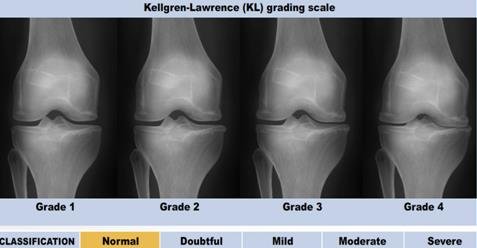

Osteoarthritis (OA) yang dikenal orang awam sebagai pengapuran sendi merupakan peradangan kronis yang terjadi karena faktor usia sehingga tulang rawan semakin menipis. Menurut dr. Nelfidayani, Sp.KFR, dokter spesialis di Klinik Patella, OA bersifat progressive degenerative joint disease sehingga tidak bisa disembuhkan dan hanya bisa dikontrol nyerinya dan mengamati progresivitasnya.